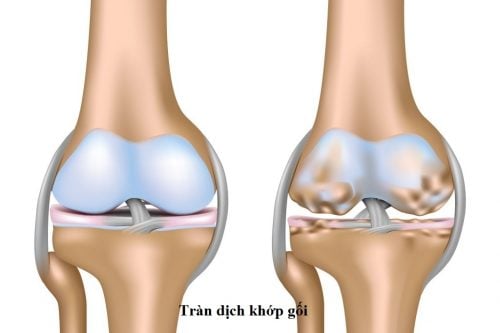

Chi phí mổ rách sụn chêm bao nhiêu?

Chi phí mổ rách sụn chêm bao nhiêu là băn khoăn của nhiều người. Bài viết dưới đây sẽ giúp bạn giải đáp những thắc mắc này cụ thể nhất. 1. Mổ rách sụn chêm như thế nào? Sụn chêm là một thành phần quan trọng trong khớp gối. Sụn chêm có thể bị rách […]

Dấu hiệu rách sụn chêm đầu gối là gì?

Sụn chêm là thành phần quan trọng ở đầu gối và rất dễ rách khi bị tai nạn hoặc chấn thương khi chơi thể thao. Vậy dấu hiệu rách sụn chêm đầu gối là gì? Dấu hiệu rách sụn chêm đầu gối là gì? Sụn chêm là một trong những thành phần quan trọng của […]

Điều trị rách sụn chêm kịp thời hiệu quả tránh biến chứng

Điều trị rách sụn chêm cần được tiến hành sớm và kịp thời hiệu quả tránh biến chứng nguy hiểm ảnh hưởng đến sức khỏe, làm hạn chế khả năng vận động. Khớp gối là một khớp phức hợp, lớn và chịu toàn bộ tải trọng của cơ thể. Vì được cấu tạo phức tạp, […]